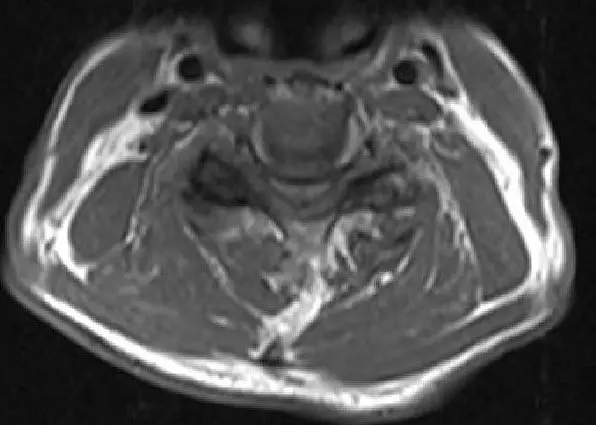

MRI T2 image Axial cut showing severe spinal cord stenosis and compression at C3-4

MRI T2 image Axial cut showing severe spinal cord stenosis and compression at C3-4